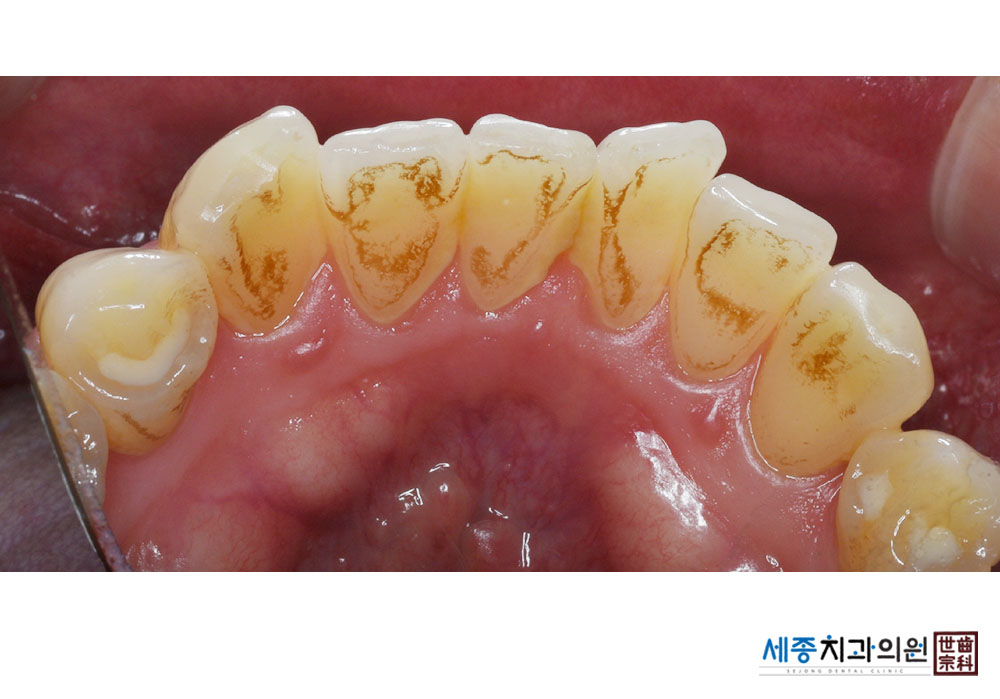

[스케일링] 치주질환 예방 스케일링

치료전 : 2023-10-23

가글마취&저주파 스켈러를 사용한 착색제거 스케일링